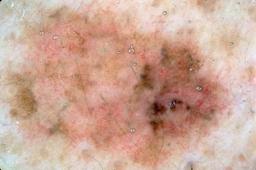

{

"age_approx": 70,

"anatom_site_general": "upper extremity",

"concomitant_biopsy": true,

"dermoscopic_type": "contact non-polarized",

"diagnosis_1": "Benign",

"diagnosis_2": "Benign melanocytic proliferations",

"diagnosis_3": "Nevus",

"diagnosis_4": "Nevus, Combined",

"diagnosis_confirm_type": "histopathology",

"image_type": "dermoscopic",

"lesion_id": "IL_5477327",

"melanocytic": true,

"patient_id": "IP_3514971",

"sex": "female"